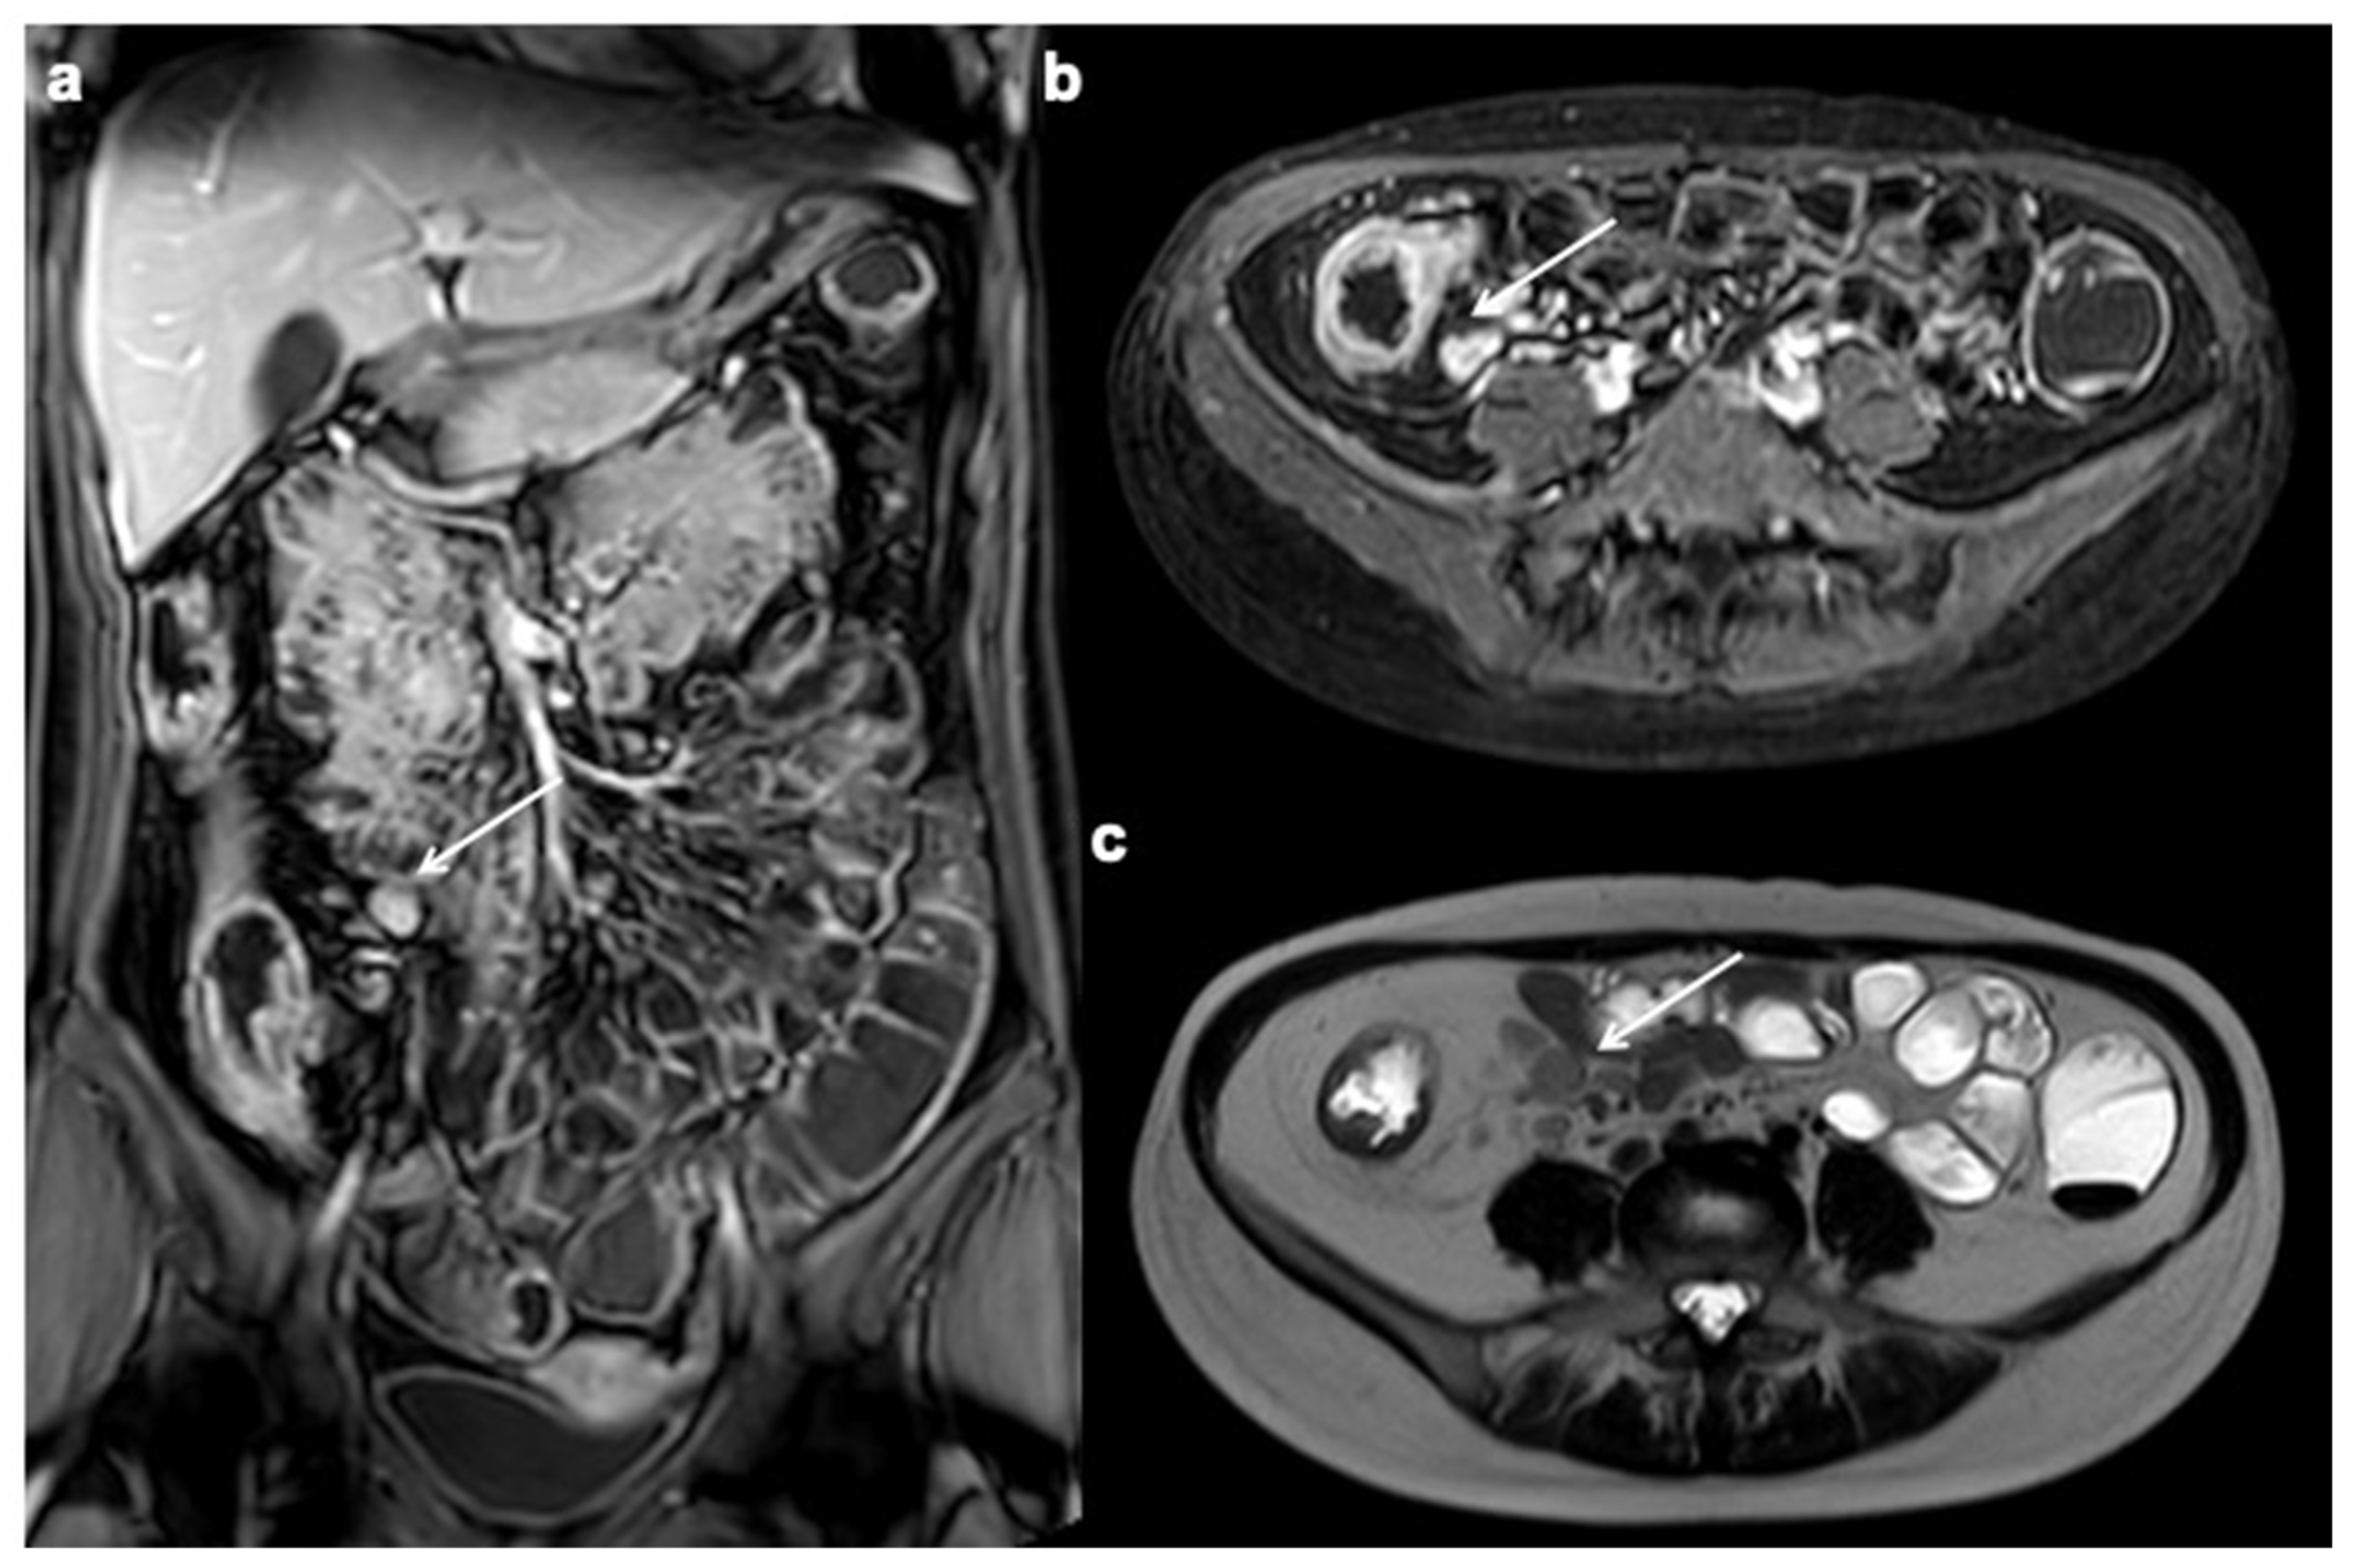

11. Imaging Findings Associated with Penetrating CD Inflammation and Complications

12. Imaging Findings Associated with Non-Active CD Inflammation